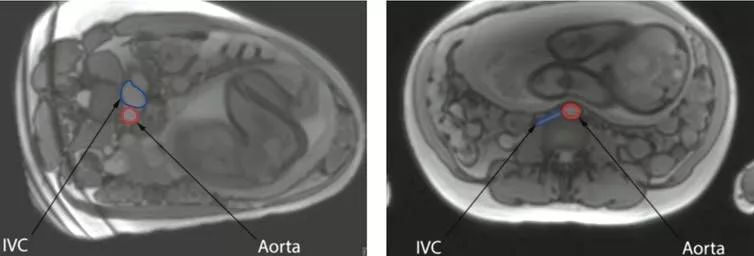

母亲平躺着睡觉和死产之间的关系在生物学上是可信的。怀孕晚期仰卧位与子宫的血流量减少有关。奥克兰大学最近进行的一项研究为母亲的睡姿如何影响血液流动提供了更成熟的证据。磁共振成像(MRI)结果显示,当孕妇仰卧时,子宫会挤压孕妇腹部的主要血管下腔静脉。这就减少了80%流经血管的流量。

MRI图像显示下腔静脉(IVC)为蓝色,主动脉为红色。在左边的图像中,母亲是左侧卧,而在右边的图像中,她是仰卧。